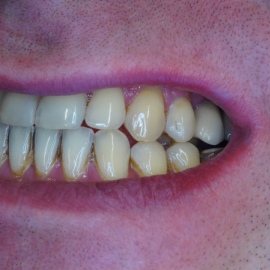

Pacjentka lat 58, prowadzi aktywne życie zawodowe. Odczuwała dyskomfort przy użytkowaniu protezy, dodatkowo przy uśmiechu odsłaniała klamry utrzymujące protezę.

implanty stomatologiczne implanty stomatologiczne implanty stomatologiczne implanty stomatologiczne